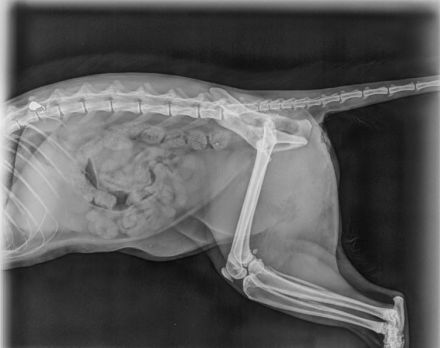

Dort wurde sie geröntgt und man stellte fest, dass ein Geschoss in ihrer Wirbelsäule steckte. Es wurde auch noch ein CT gemacht, um zu erkennen, ob eine Operation hilfreich wäre.